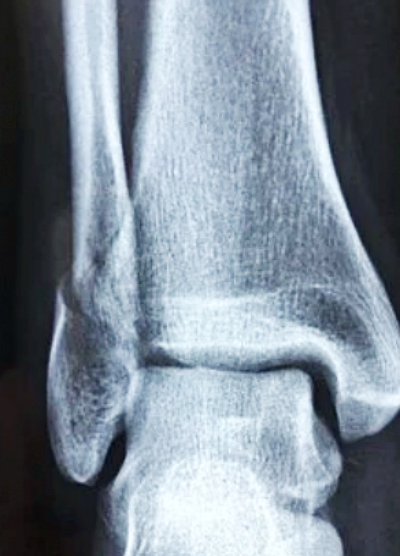

골다공증

골다공증이란 뼈 속에 있는 칼슘이 빠져 나가게 되면서 뼈의 밀도가 줄어드는 것을 말합니다. 사람은 나이가 들어감에 따라 성 호르몬이 줄어들면서 몸에서 점점 칼슘이 빠져 나가게 되죠. 또한 비타민 D 의 부족으로 인해서 골다공증이 생길 수도 있습니다.

우리 몸은 각 부위에 맞는 충분한 영양소가 흡수 되어야 하는데 그것들이 부족하게 되면 뼈의 구멍이 뚫리는 골다공증이 생길 수도 있는 것입니다.

골다공증이 생기면 당연히 뼈가 약해지고 그 사이로 바람이 스며들어 시린 증상과 뼈가 부러진은 증상들이 나타날 수 있습니다. 골다공증 예방을 위하여 어떤 음식이 좋은지 골다공증에 좋은 음식에 대해서 알아보겠습니다.